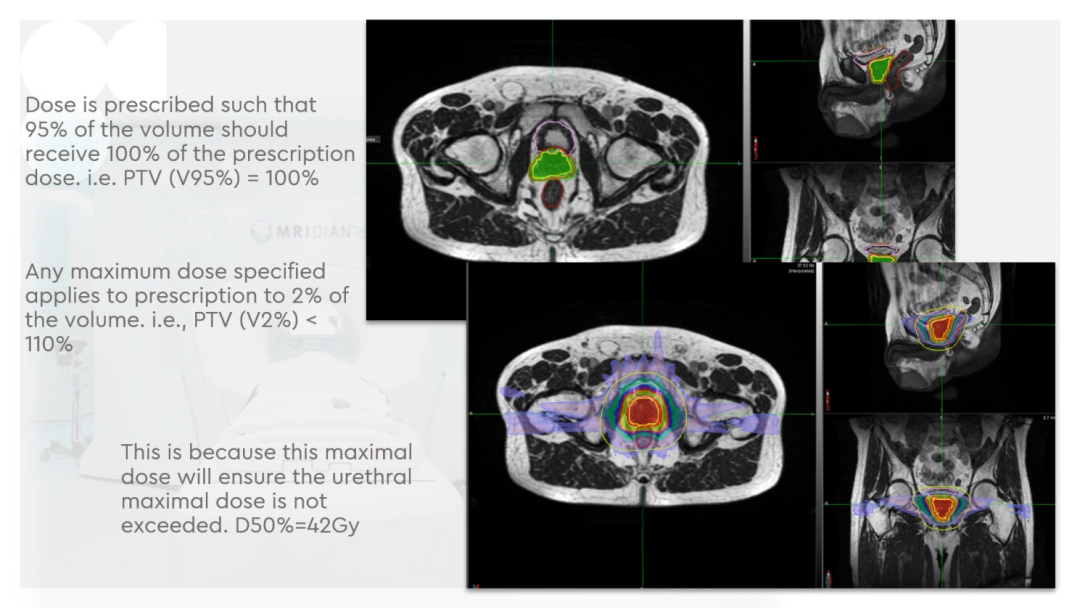

Dr. Camilleri表示,他们在做在线自适应放疗的时候,为了提高速度,仅对靶区外放3cm以内的危及器官的变化进行自适应调整或重新勾画轮廓,见Figure 13。这样可以缩短轮廓勾画的时间。对于放疗计划,使得95%的靶区体积接受到100%的处方剂量覆盖,并将最大剂量限制为2%的靶区体积不超过处方剂量的110%,这样就能保证在图像上很难显示的尿道不会超量,见Figure 14。另外,在制作放疗计划时,将PTV分为PTV LOW和PTV High,PTV和危及器官重叠的部分为PTV LOW,将PTV LOW的剂量目标设定在危及器官的耐受剂量以下,这样就能保证危及器官不超量,见Figure 15。